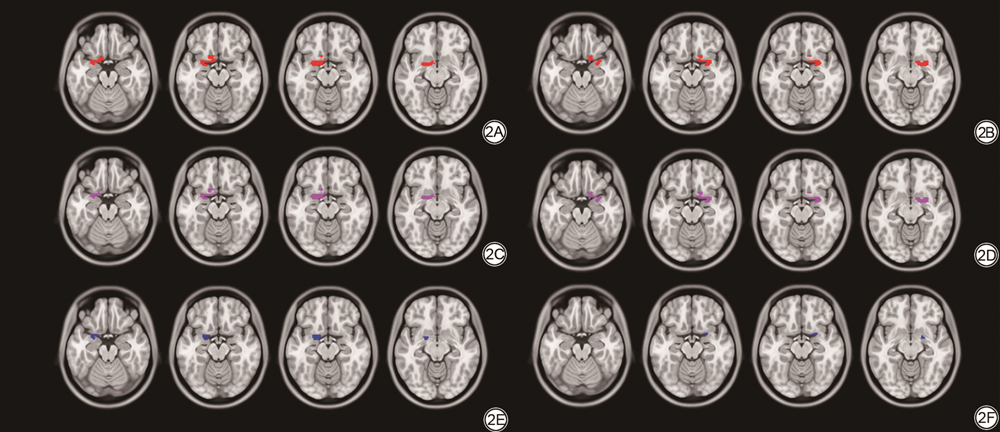

三组间双侧POC灰质体积的差异均有统计学意义(FWE多重比较校正,P<0.01),NC组双侧POC灰质体积均明显大于AD组,组间比较结果详见图2。三组间左侧海马灰质体积的差异均有统计学意义(Bonferroni校正,P<0.05);NC组和AD组、MCI组和AD组间右侧海马、双侧杏仁核、双侧岛叶、右侧眶额皮质灰质体积的差异均有统计学意义(Bonferroni校正,P<0.05),上述结构在NC组和MCI组间的差异无统计学意义(Bonferroni校正,P>0.05);左侧眶额皮质灰质体积在NC组和AD组间的差异有统计学意义(Bonferroni校正,P<0.05),在MCI组和AD组、NC组和MCI组间的差异无统计学意义(Bonferroni校正,P>0.05)。统计结果详见表2。